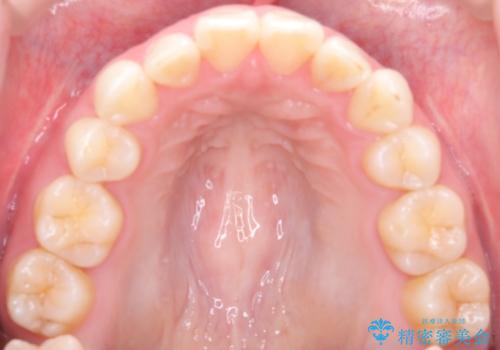

【抜歯インビザ】前歯の凸凹をなおしたい

- 前歯の凸凹を主訴に来院されました。

前歯はあまり下げる必要がなかったため、上下左右の第二小臼歯抜歯を行う治療計画としました。

途中、臼歯の近心傾斜を認めましたが、追加アライナーを使用することでリカバリーを行いながらインビザラインのみで治療を完了することができました。